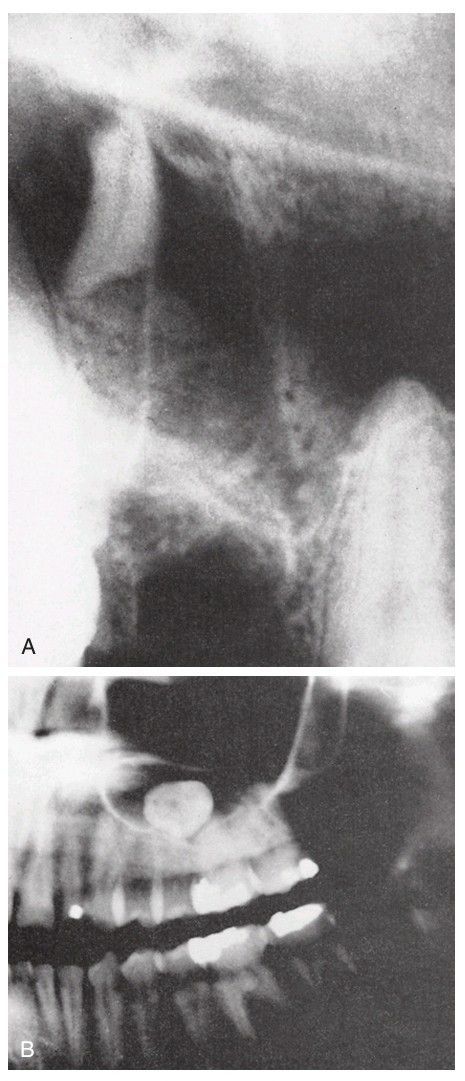

(A) Large root fragment displaced into the maxillary sinus. The fragment should be removed by the Caldwell-Luc approach or sinus endoscopy. (B) The tooth in the maxillary sinus is the maxillary third molar that was displaced into the sinus during elevation of the tooth. This tooth must be removed from the sinus, potentially by the Caldwell-Luc approach.